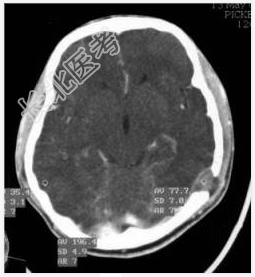

- [材料题] 病历摘要:男性,20岁。

主诉:发现头皮软组织肿物3个月。

现病史:三月前发现左枕部软组织轻微突起伴隐痛,到当地医院检查发现左枕部颅骨骨质缺损,未作具体治疗,现觉头皮肿物增大,时伴有气促、头痛。

专科检查:左颞枕部软组织略膨起,较软,各项病理反射(-)。

- 简答题1、诊断及诊断依据是什么?